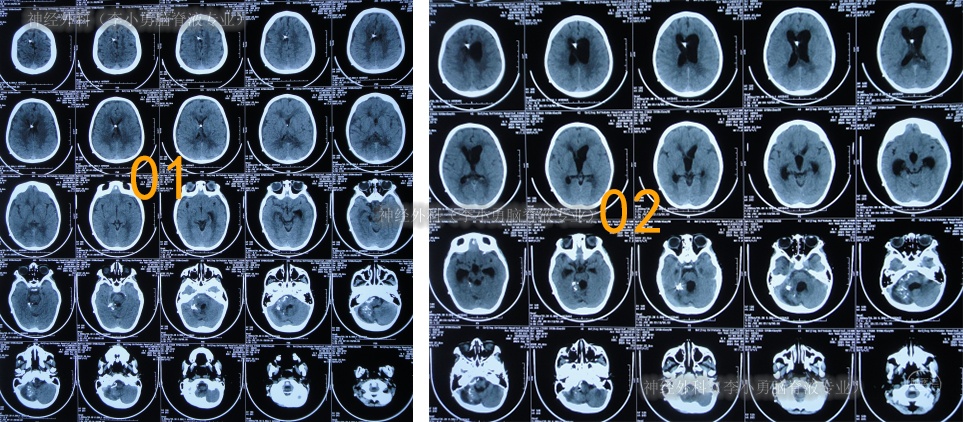

术后半月余期间3次查头颅CT(图-3)均示脑室仍扩张。

图-3:3次查头颅CT

入院后10天即2024年6月12日,查头颅CT示脑室有所缩小(图-9)。

图-9:2024年6月12日头颅CT

入院后12天即2024年6月14日,头颅CT示脑室进一步缩小(图-10);意识变得完全清楚能喊爸爸妈妈,能回答(图-11)。

图-10:2024年6月14日头颅CT